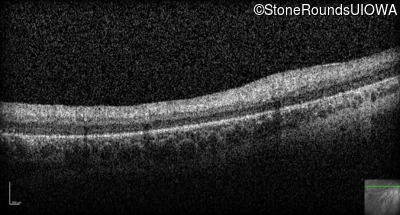

Optical Coherence Tomography - Left -

No Light Perception

Exemplar

Optical Coherence Tomography - Right -

Light Perception